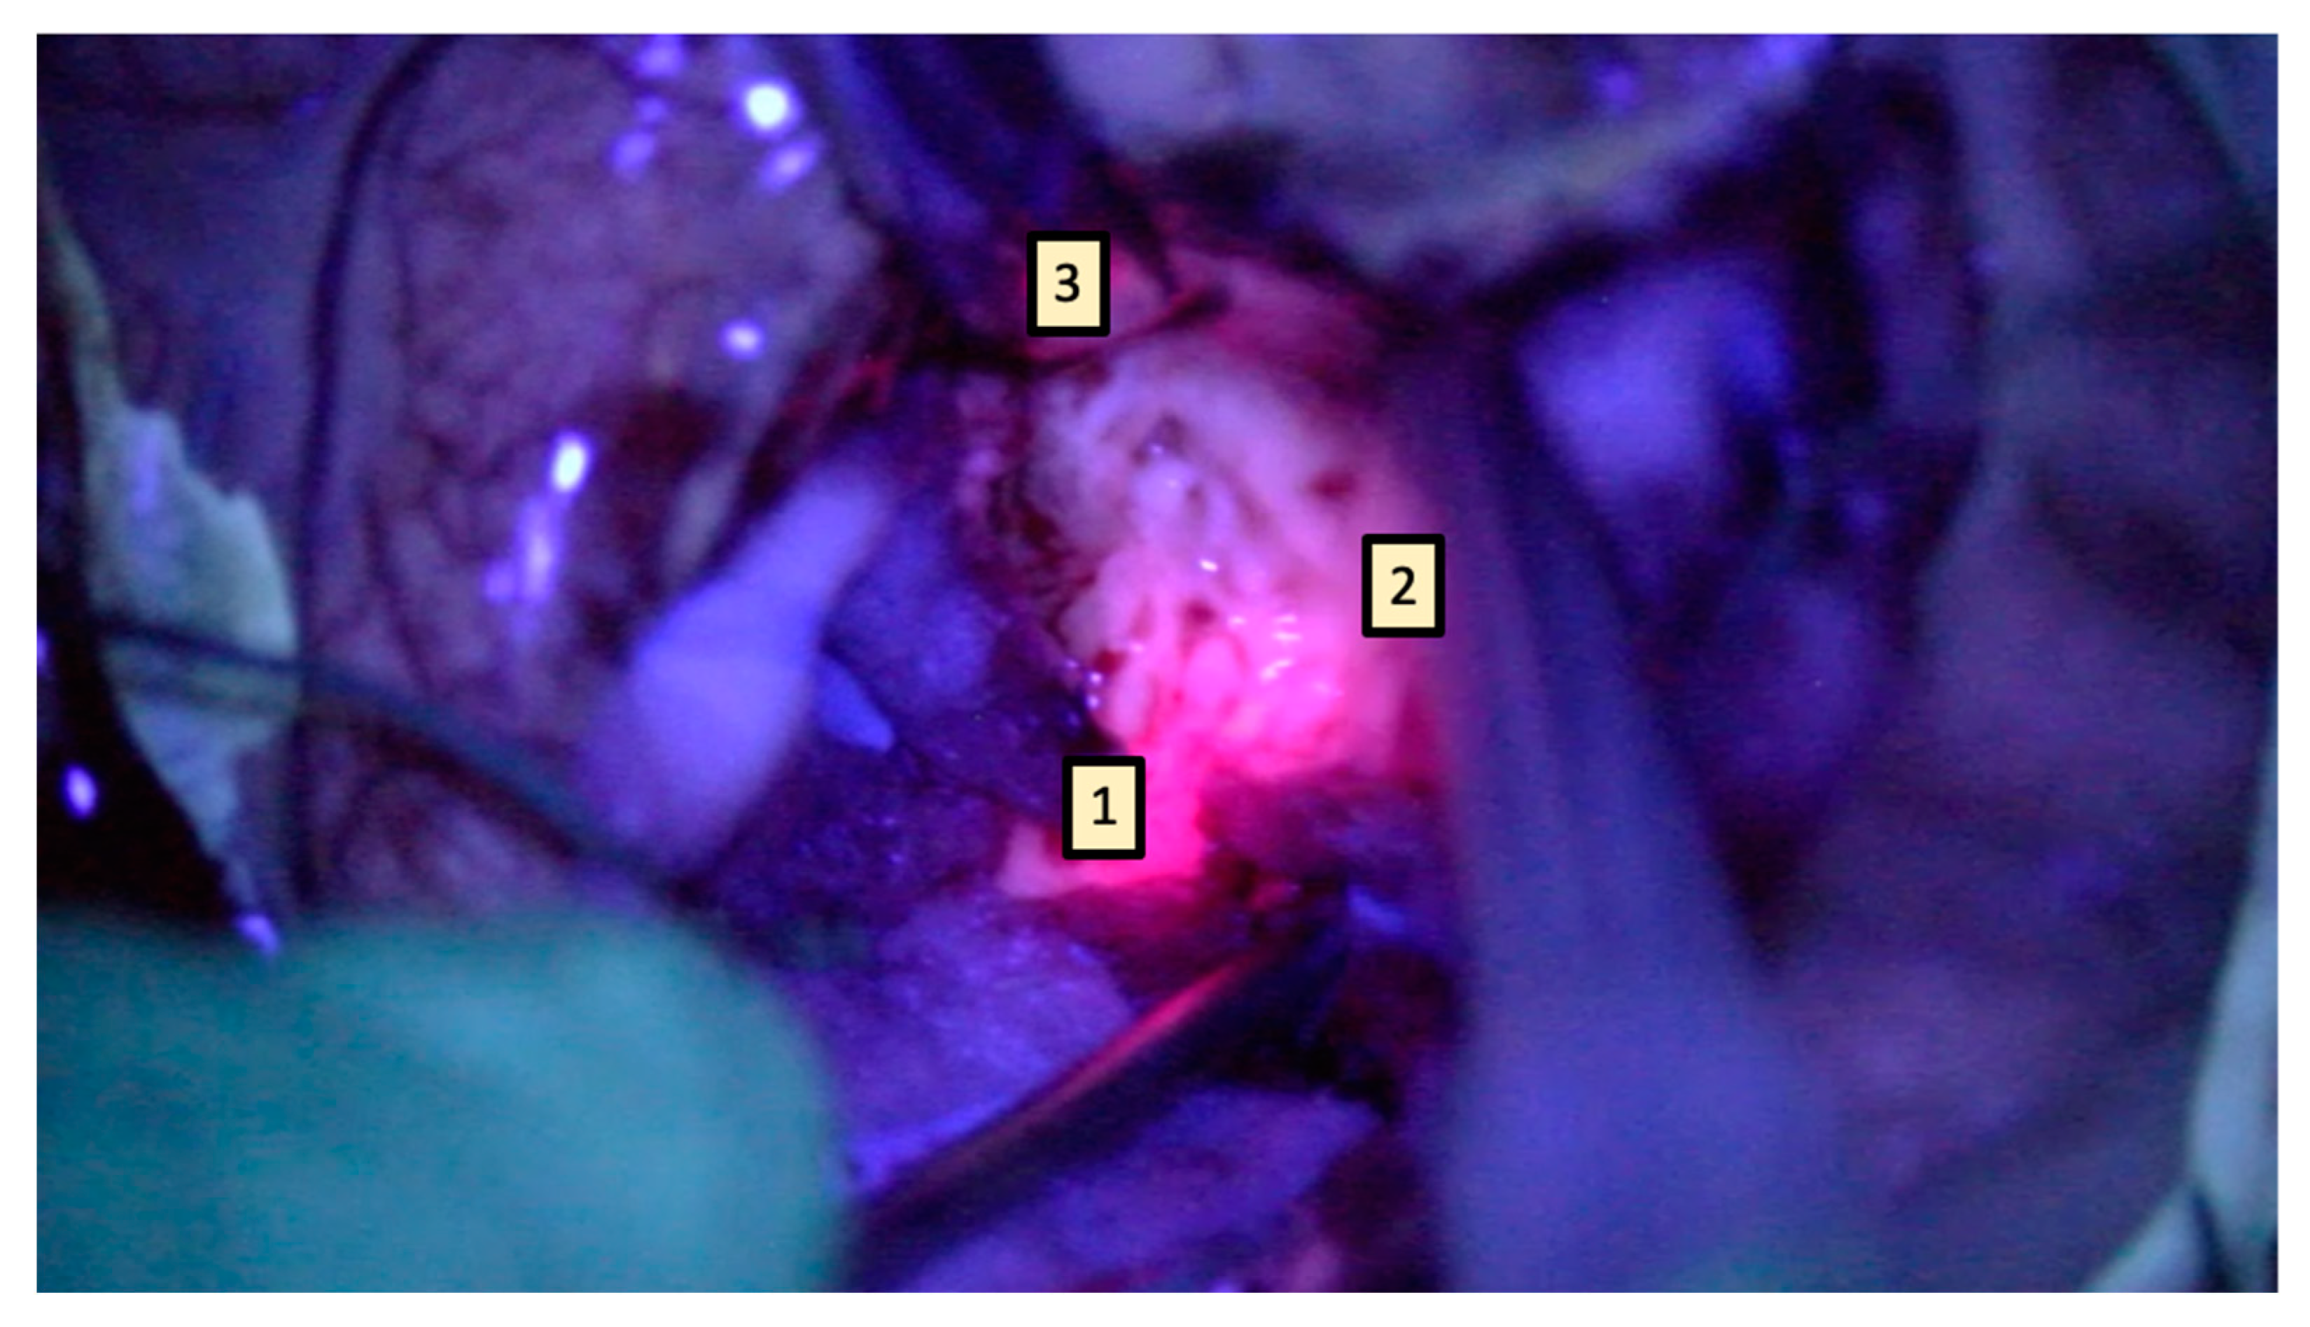

It is known that the core of the tumor displays a clear “lava red” appearance, generally corresponding to gadolinium enhancement, while surrounding tissue displays a “pale” fluorescence. This “pale” area, extending over the limits of radiological enhancement, is a fertile soil for pathological infiltration. Where feasible, resection should also include these zones [15,16,17]. In other words, 5-ALA guidance is paramount in the final stages of surgery, whereas most of the procedure should be carried out under normal white light. However, especially with surgeons who are not routinely experienced with 5-ALA use, this might lead to a greedy approach, “chasing” fluorescence. This means that the surgical cavity should be carefully explored with blue filter only at the end of gross total resection in order to identify remnants to be resected if functionally feasible. It should always be kept in mind that functional integrity represents the true limit of resection and the procedure, especially in these final stages, should be supplemented by neurophysiological subcortical stimulation if necessary [18] (Figure 5).

Figure 5.

Research suggests that 5-ALA has mainly a refinement role after gross resection. The lava red area represents the tumor core (1) and the pale area represents the infiltrative margins (2), surrounded by the negative fluorescent area (3). Where feasible, it is paramount to extend resection, including the peritumoral “pale” area, without pushing it over neurophysiological boundaries.